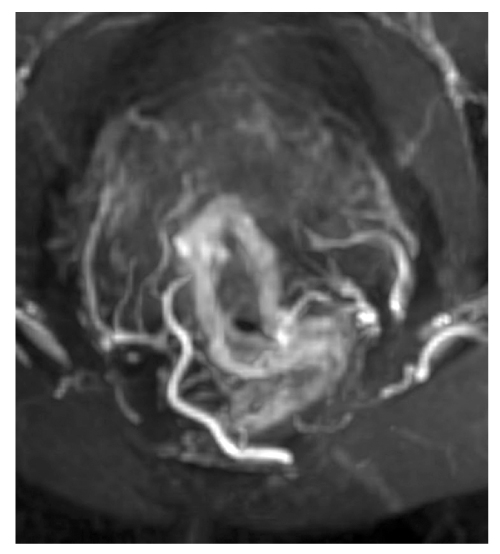

Следует отметить, что в 1/3 (34%) случаев определялось по 2 ветви верхней прямокишечной артерии с последующей трифуркацией, причём задние ветви отходили в виде дуг к задней стенке кишки на 5 и 7 часах условного циферблата — вариант 2. На рис. 6 изображены первый и второй варианты. Так же редко, всего в 2 наблюдениях, отмечалась сосудистая аркада в виде дуги, питающая почти всю окружность кишки по типу кровоснабжения тонкого кишечника — вариант 3 (рис. 7). Чуть более часто, в 6 случаях, наблюдался рассыпной тип с одновременным или последовательным отхождением от верхней прямокишечной артерии 6 отдельных ветвей к стенке кишки — вариант 4 (рис. 8). В 4% случаев наблюдалось по 4 ветви верхней прямокишечной артерии, 2 из которых формировали бифуркации, а 2 шли отдельно — вариант 7.

Рис. 7. Артериальная аркада стенки прямой кишки: MIP-реконструкция магнитно-резонансной томографии.